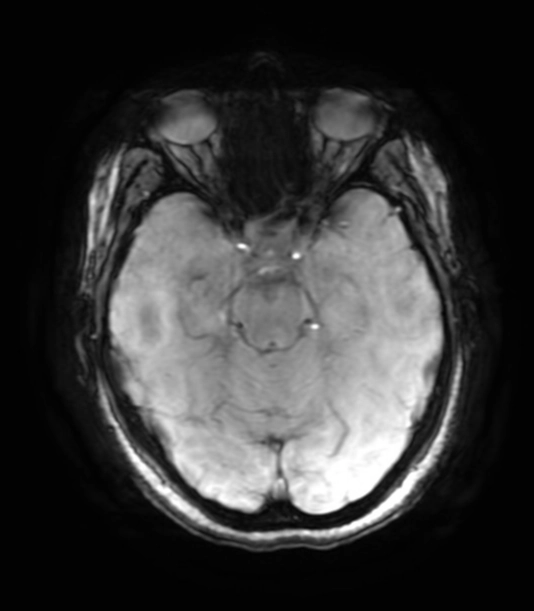

Tổn thương sợi trục lan tỏa (Diffuse Axonal Injury - DAI)

Phân độ tổn thương sợi trục lan tỏa(Diffuse Axonal Injury Grading)